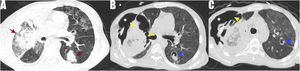

During the follow-up of the immunosuppressed patient who continued to receive chemotherapy for T-cell lymphoma, decreased saturation values, respiratory distress and hemoptysis were observed. Follow-up CT scan showed diffuse ground-glass densities in both lungs. Red arrows indicate ground-glass densities and consolidated areas (Fig. 1A). Yellow arrows indicate pleural rupture, white asterixes indicate massive subcutaneous emphysema, yellow curved arrow indicates bronchopleural fistula, and blue arrowheads indicate different aspergillomas showing air crescent. (Fig. 1B and C). CT evaluation showed that the large cavitary lesion in the right lung had progressed to the adjacent pleura and ruptured to form a bronchopleural fistula, and the free air in the cavity caused massive subcutaneous emphysema. Invasive aspergilloma progresses very rapidly, especially in immunosuppressed patients.

Computed tomography of the immunocompromised patient showed diffuse ground-glass densities in both lungs. Red arrows show ground-glass densities, consolidated areas (A). Yellow arrows show pleural rupture. White asterisks indicate the area of subcutaneous emphysema, yellow curved arrow indicate bronchopleural fistula, blue arrowheads indicate different aspergillomas showing the air crescent (B and C).